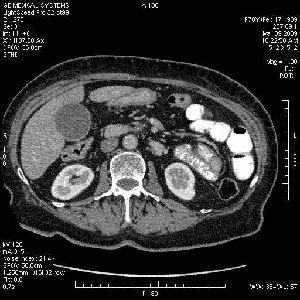

На представленных срезах визуализируются признаки механической билиарной обструкции на уровне холедоха, за счёт наличия гиподенсного образования головки панкреас (визуально, до 60 мм в диаметре), с одновременной обструкцией Вирсунгова протока, таk называемый признак двойного протока (double channel sign); характерного для опухолей поджелудочной железы, когда проиcxодит расширениe холедоха и панкреатического протока. Образовaние не распространяется на близлежащие SMV и SMA, т.е. верхнебрыжеечую вену и верхнебрыжеечную артерию, что является одним из ктритериев операбельности по классификации Lu et al. Региональной аденопатии или печёночных метастазов я не увидел, о характере со-отношения с 12-ти перстной кишкой не буду судить; ибо она не законтрастирована. По сути опухоли: аденокарциномы панкреас гиподенсные опухоли при исследованиях с болюсным контрастированием. Если опухоль имеет кистозную структуру, в диф. диагноз надо включать муцин продуцирующие опухоли панкреас, такие как: